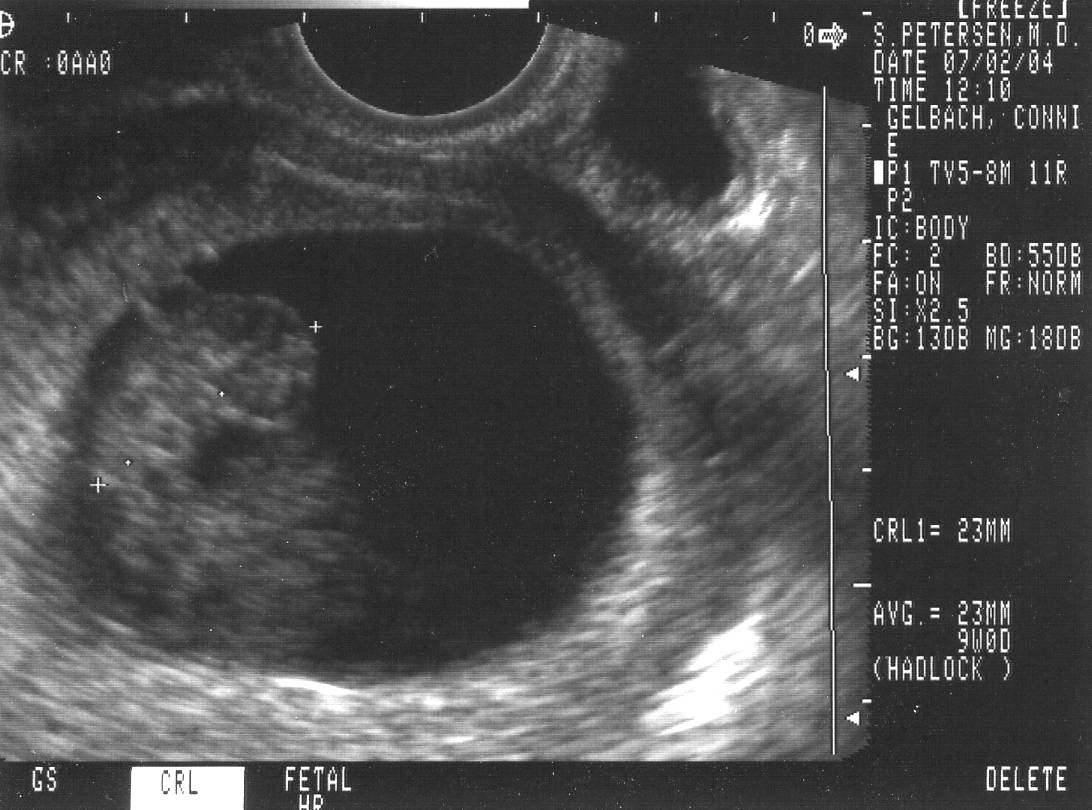

Sonograms